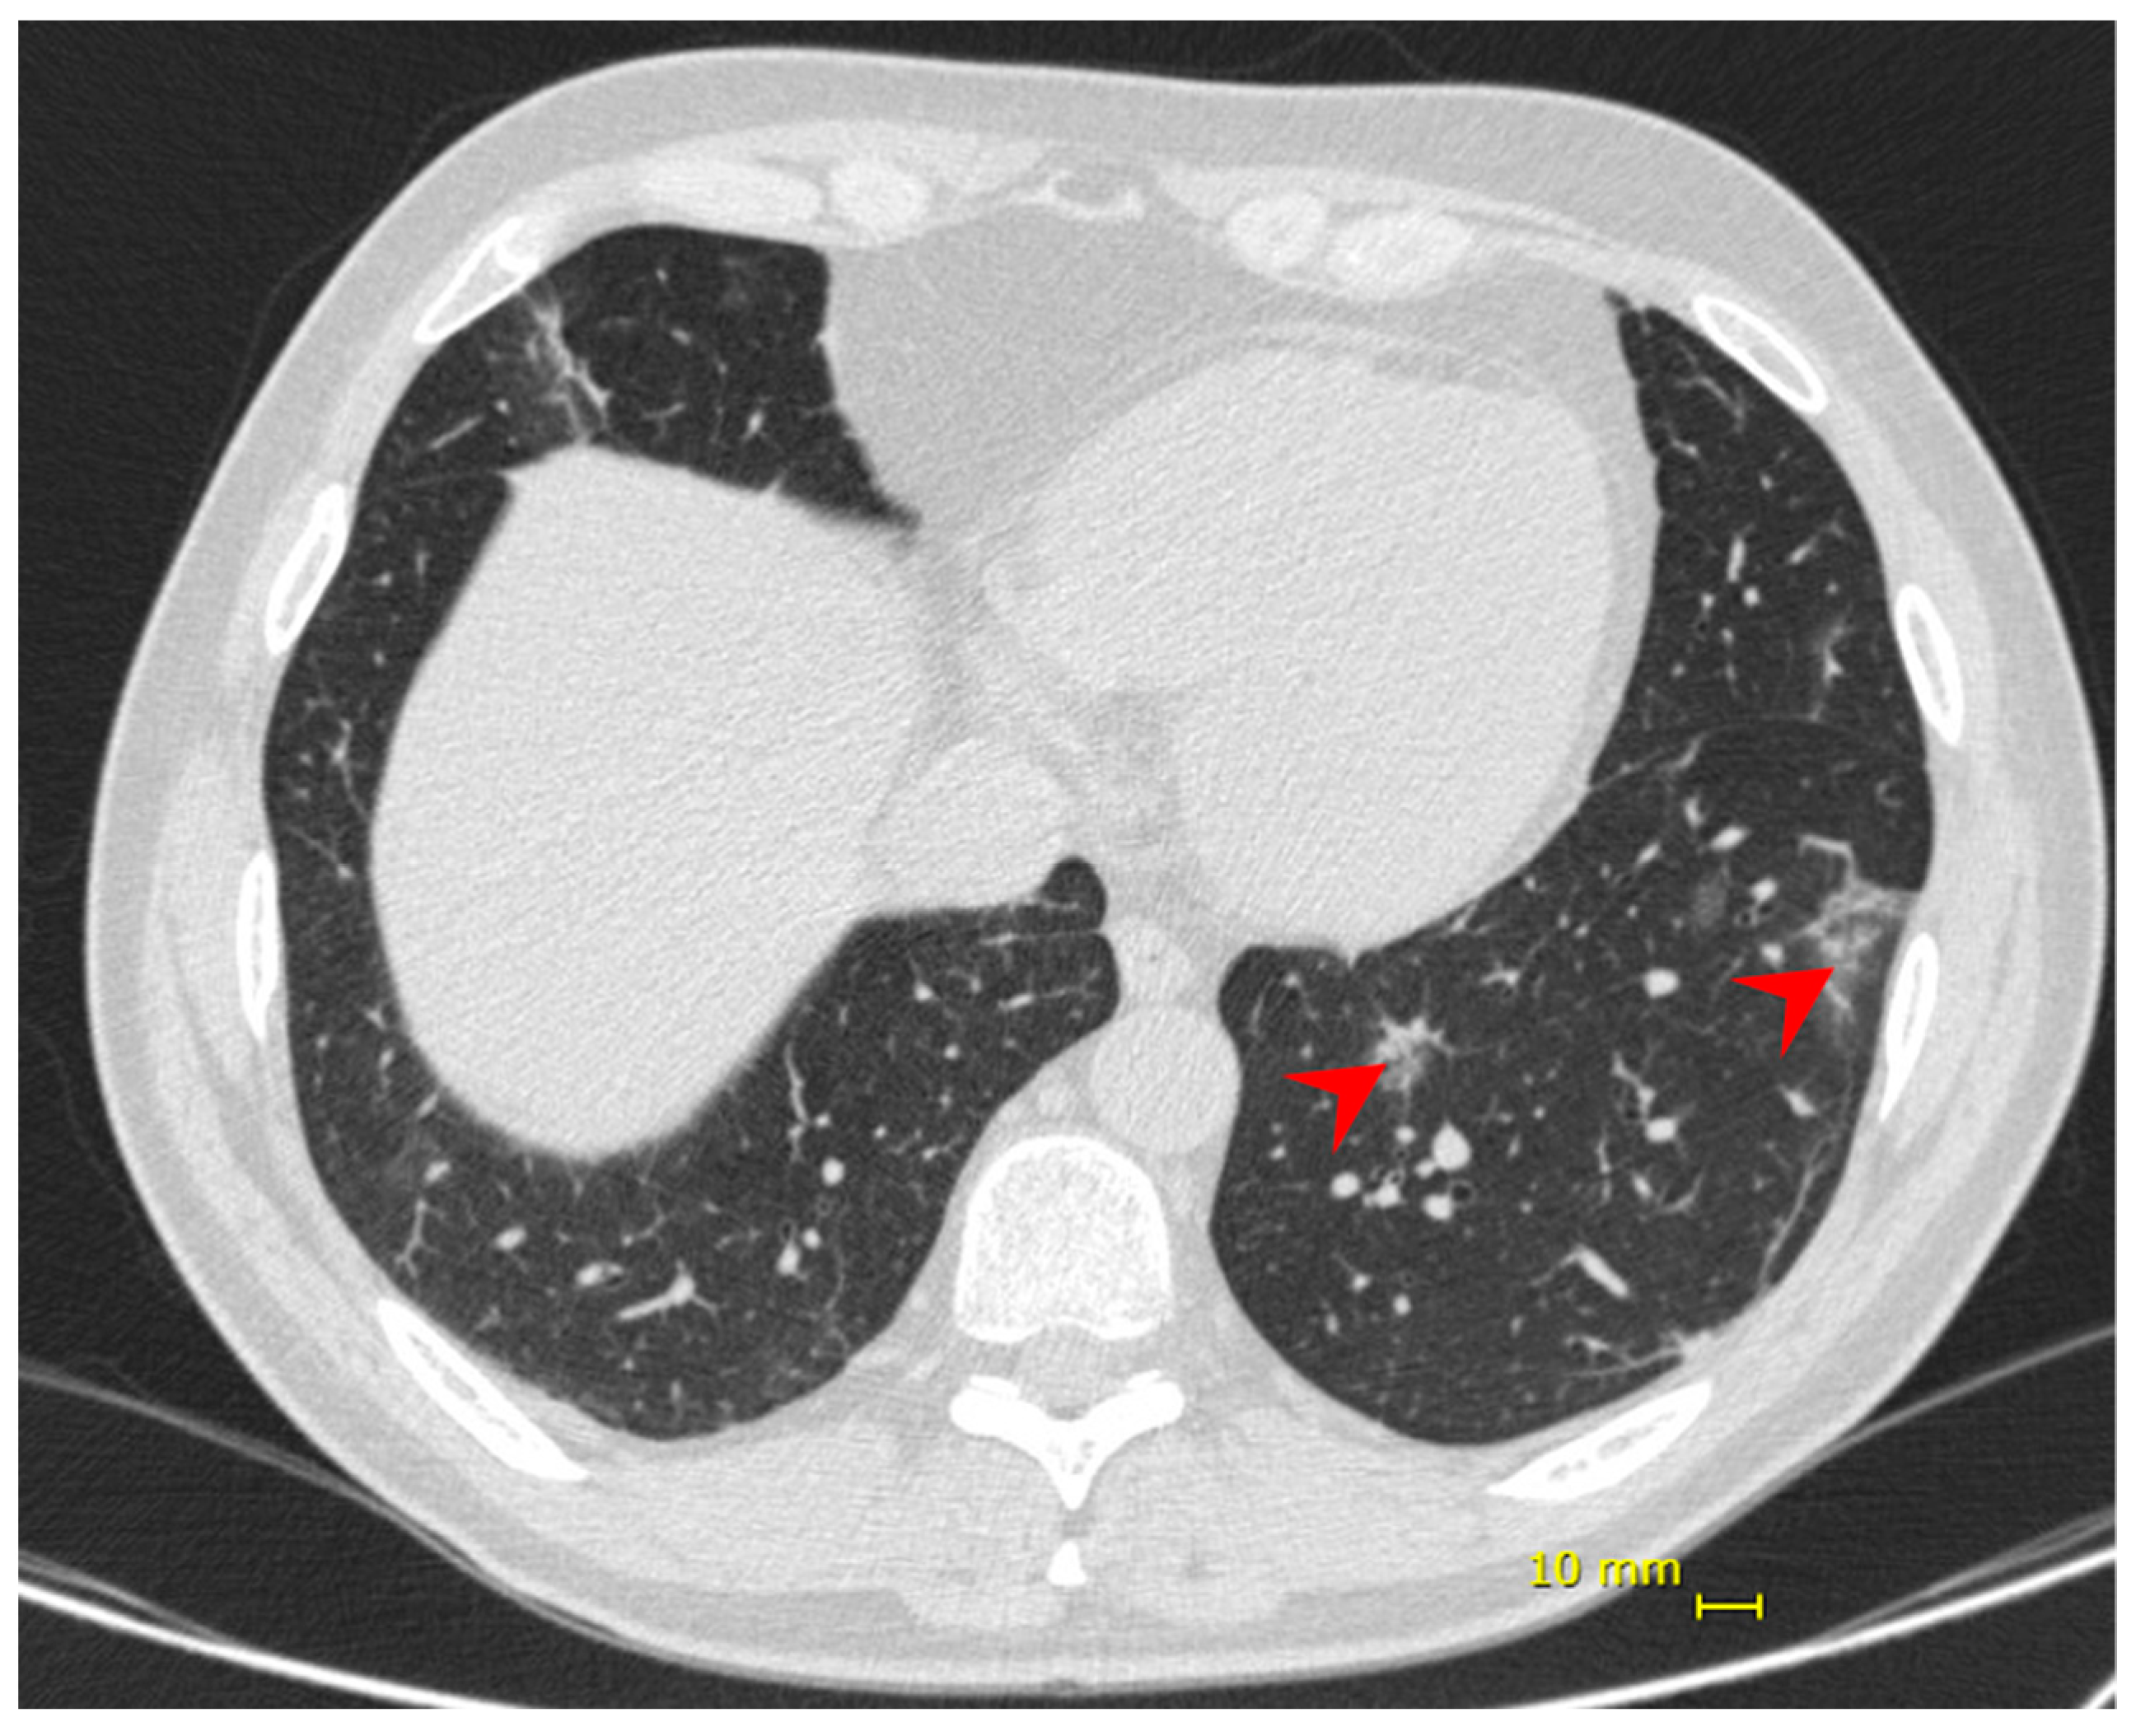

| Chest CT | Bilateral multifocal ground-glass opacities (25–50%) predominantly peripheral and subsegmental atelectasis | Bilateral multifocal ground-glass opacities (<25%) predominantly peripheral, and subsegmental atelectasis | ||||||